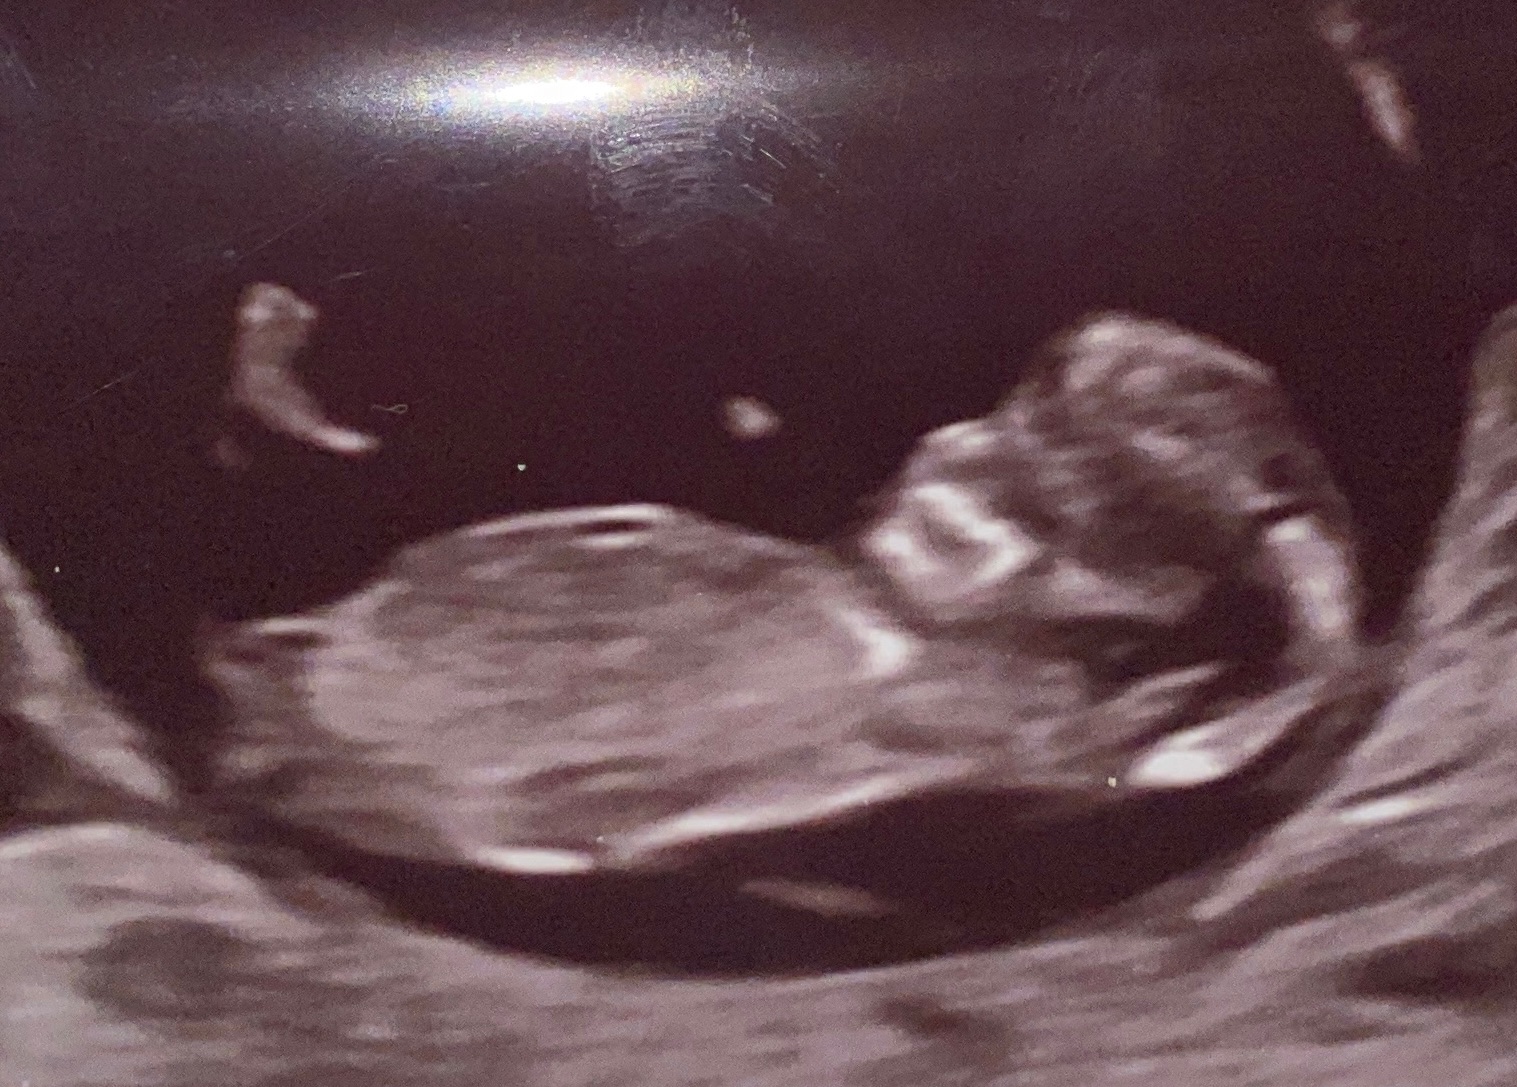

byla jsem na ultrazvuku 10+5tt a doktorka mi řekla, že vidí větší šíjové projasnění - neřekla kolik.

Přikládám foto ultrazvuku. Myslím, že to tam je dost vidět.

děkuji za Váš dotaz. Bohužel ze snímku toho říci moc nelze. Kromě toho posuzovat tloušťku šíjového projasnění je na místě podle standardizovaných podmínek mezi 11+0 až 14+0 (při temeno-kostrční délce embrya 45-84 mm) a spíše v druhé polovině tohoto intervalu než hned z počátku. Určitě tedy vyčkejte na řádné provedení prvotrimestrálního screeningu podle doporučení.